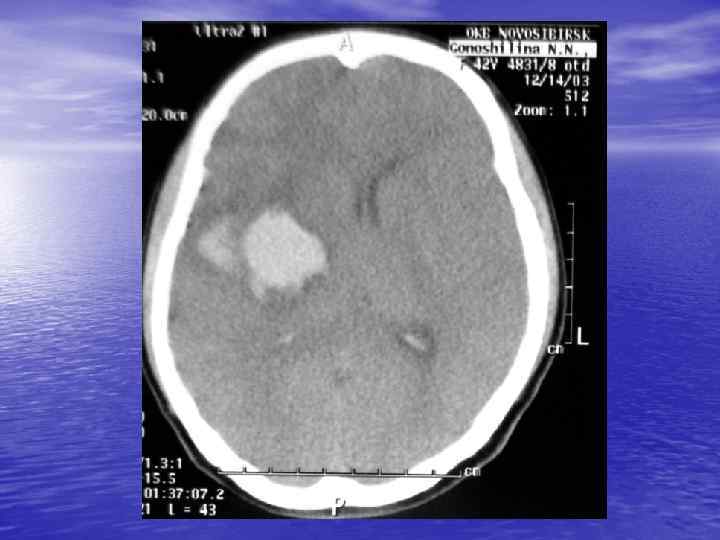

Преимущества спиральной КТ: ü Возможность проведения исследования с болюсным ü ü ü ü ü контрастированием Высокая разрешающая способность; Высокая скорость исследования; Получение высококачественных изображений костных структур; Возможность обследования всего тела; Возможность проведения исследования больных под наркозом; Возможность детальной оценки состояния крупных и периферических сосудов в условиях искусственного контрастирования; Высокая информативность метода при черепномозговых травмах в остром периоде; Ранняя диагностика ишемических и геморрагических инсультов; Метод выбора для диагностики заболеваний легких; Планирование лучевой терапии.